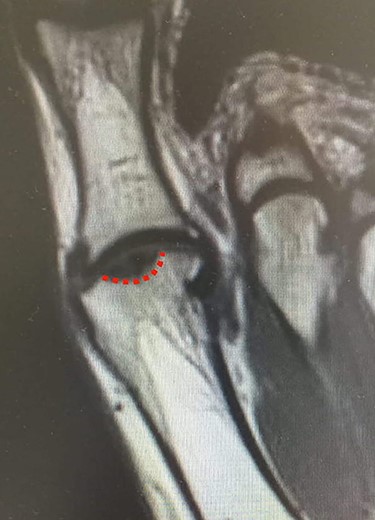

MRI of the left foot, shows low signal intensity lesion on the MH. The red dots show the depth of a subchondral cyst formation.

MRI (sagittal view) of the left foot. The red dots show a deep MH defect involving the subchondral bone, a typical finding of OD.

Standing anteroposterior (AP), oblique and lateral radiographs of the affected foot were taken. On the AP and oblique views, an OD lesion of the 1st MH was visible (lytic lesion of the subchondral bone and subchondral sclerosis formation) with a lateral-forming osteophyte (Fig. 1A and B). Magnetic resonance imaging (MRI) of the left foot clearly shows the osteochondral defect of the 1st MH (Figs 2 and 3).